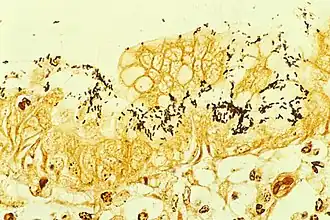

Tinción inmunohistoquímica de Helicobacter procedente de una biopsia estomacal.

La infección por H. pylori puede ser sintomática o asintomática (sin efectos visibles en el enfermo); se estima que más del 70 % de las infecciones son asintomáticas.[15]​ En ausencia de un tratamiento basado en antibióticos, una infección por H. pylori persiste aparentemente durante toda la vida. El sistema inmunitario humano es incapaz de erradicarla.